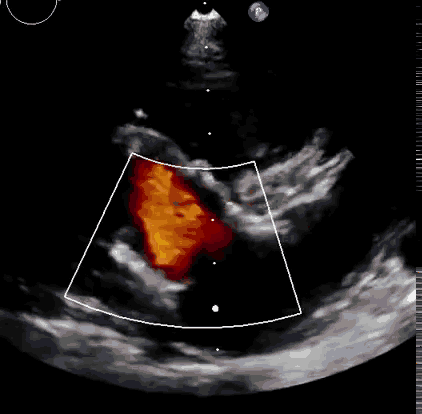

2021年11月14日星期日,復(fù)旦大學(xué)附屬中山醫(yī)院(以下簡稱中山醫(yī)院)葛均波院士團(tuán)隊(duì)成功應(yīng)用經(jīng)血管介入三尖瓣置換產(chǎn)品Lux-Valve Plus完成臨床前研究,并獲得圓滿成功!此次研究的成功預(yù)示經(jīng)血管三尖瓣產(chǎn)品Lux-Valve Plus已完成臨床前準(zhǔn)備,即將開啟后期的正式臨床研究!

上海中山醫(yī)院葛均波院士、錢菊英院長、周達(dá)新教授、潘文志教授、潘翠珍教授、李偉教授共同完成此次臨床前研究。術(shù)后葛均波院士對Lux-Valve Plus的器械操作性能給予了高度評價(jià),DSA和超聲影像也顯示出在本次研究中Lux-Valve Plus的安全性和有效性俱佳。

本次臨床前研究經(jīng)右側(cè)頸靜脈置入LuX-Valve Plus輸送系統(tǒng)可調(diào)彎鞘管,在DSA及超聲引導(dǎo)下將人工三尖瓣瓣膜植入到原有三尖瓣位置,利用獨(dú)特的錨定技術(shù)將人工瓣膜支架可靠固定在預(yù)定的位置。